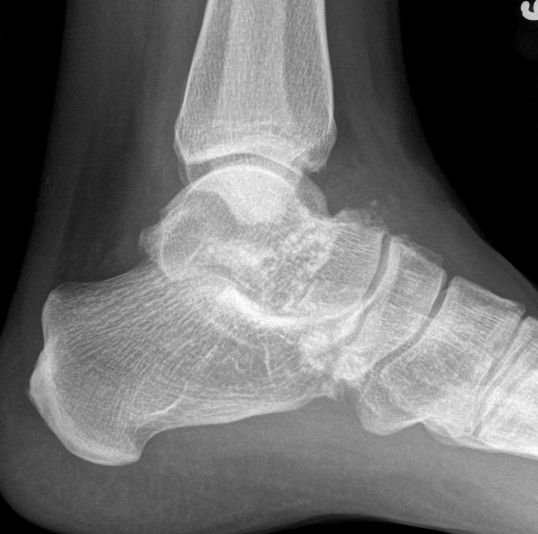

X-ray

Demonstrate calcified lesions / synovial osteochondromatosis

Synovial chondromatosis

Synovial osteochondromatosis

Ankle

Bojanic et al Foot Ankle Int 2021

- 17 patients

- 14/17 had anterior and posterior compartment involvement

- 2/17 dissatisfied

- no recurrence